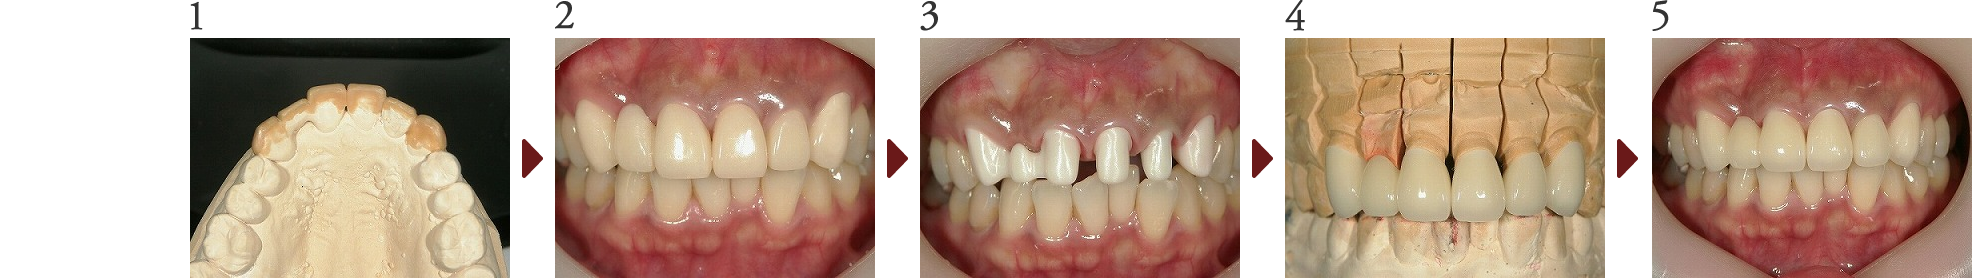

Case.2

前歯審美修復(ラミネートべニア修復 他)

患者さんは上顎前歯の歯並びの不揃い、変色、パッチワーク修復物による審美的なコンプレックスの改善を目的に、オールセラミックスによる審美修復を行う事となりました。

このように、未修復の天然歯と補綴された修復歯が混在するケースでは、歯全体の色調の調和がとれていないとバランスが悪くなり審美的とは言えなくなる為困難を要します。

今回は、オフィスホワイトニング、ラミネートべニア修復、オールセラミックスクラウン修復にて4前歯を修復しました。

また、上顎前歯未修復歯と下顎前歯との色調を調和させるため、クリスタルアイという機器によるデジタルシェードテイキング(機械的な測色)を行い、可及的に色調の調和が取れるよう治療を進めました。最終的には全体的に調和を保った修復治療になったのではないかと考えます。

(技工担当:北見市デンタルプランニング 工藤 利一氏)